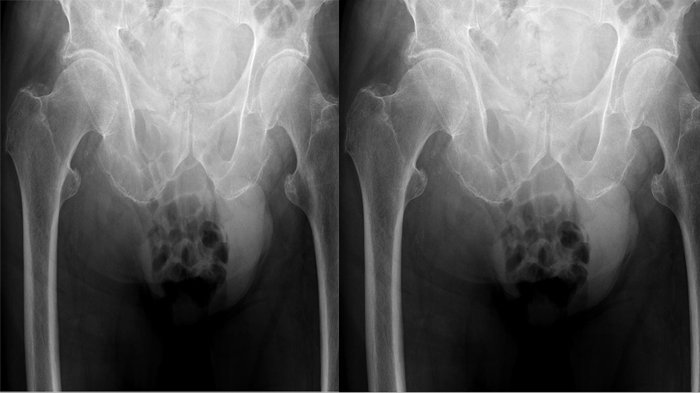

Satu diantara organ reproduksi pria ini tiba-tiba membengkak, ukurannya sebesar buah kelapa.

Buah zakar yang membengkak itu beratnya mencapai 2kg dan berada di selangkangannya.

“Benjolan itu kini menjadi beban, saya sulit untuk bergerak dan bila dipencet benjolan itu akan menjadi keras," katanya.